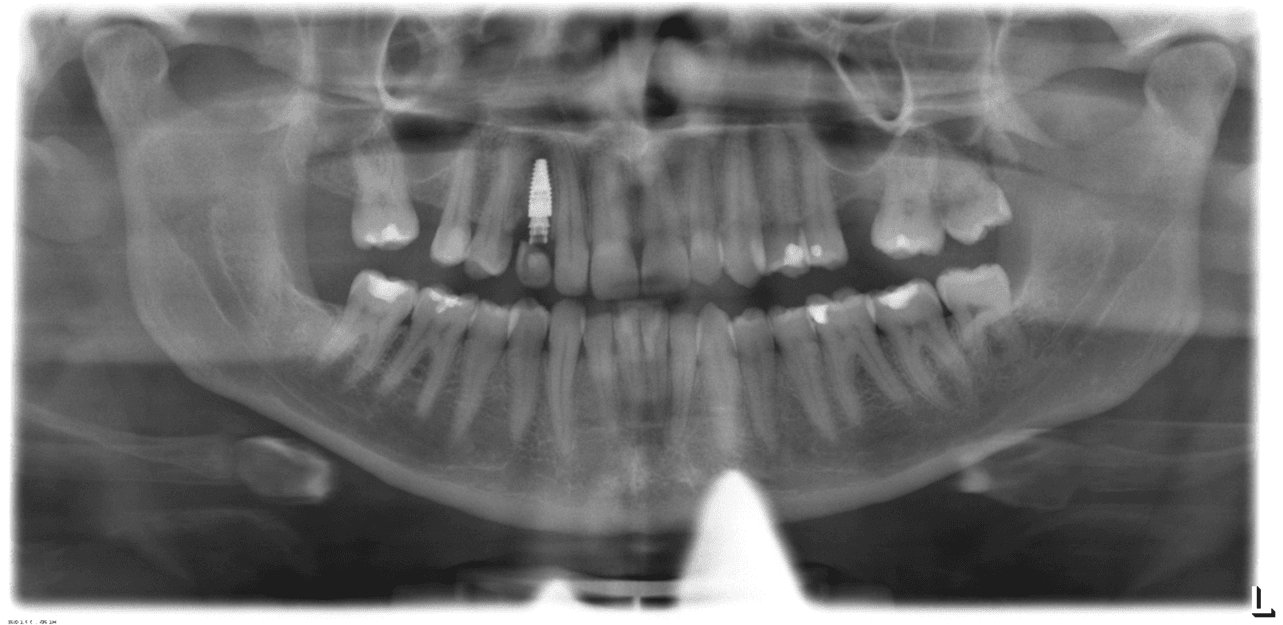

Doença Periodontal Ativa:

Pacientes com doenças gengivais avançadas podem não ser candidatos ideais para alinhadores, pois a movimentação dentária pode agravar a condição.

O tratamento ortodôntico em pacientes com doença periodontal deve ser realizado com muito critério e cuidado, sendo contraindicado o tratamento ortodôntico em pacientes com doença periodontal ativa.

Perda Óssea Significativa:

A perda óssea ao redor dos dentes pode comprometer a capacidade do alinhador de mover os dentes de forma eficaz e segura.

A movimentação ortodôntica pode exacerbar essa mobilidade, o que aumenta o risco de complicações como a perda do dente ou uma piora da condição da gengiva.